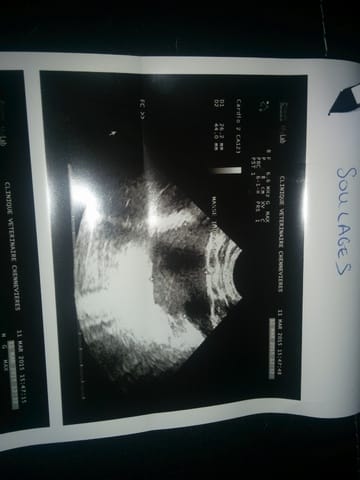

Je l’ai emmené chez le vétérinaire et le résultat après analyse est qu’il a une masse très grosse qui compresse son cœur.

Je dispose des échos représentant la masse qui pose problème.